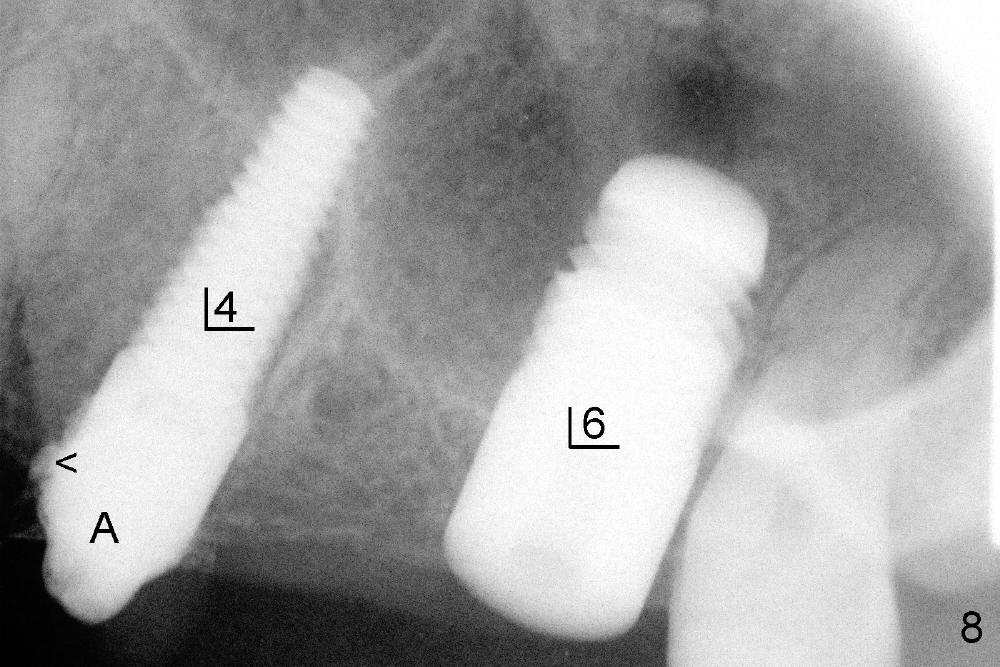

An immediate implant was tried at the site of the 1st molar without success 2 weeks earlier. One month after 1st try, a 7x14 mm cylindrical implant is placed (Fig.8). There is a space issue: the mesial surface of the 2nd molar has to be trimmed in order to place the large implant at the 1st molar (Fig.9). A 4.5x11 mm tapered implant is placed at the 2nd bicuspid at the same apppointment (Fig.9). Both implants have barely enough primary stability. No immediate provisionals are fabricated. In fact there should no problem doing so, considering 3 neighboring implants. Splinting can compensate for lack of primary stability in 1 or 2 implants.